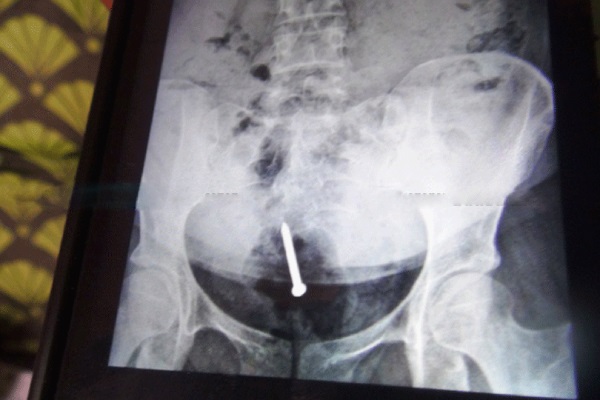

மருத்துவர்கள் தன்னை பரிசோதித்தபோது, வயிற்றில் ஐந்து இரும்பு ஆணிகள் இருப்பதைக் கண்டதாகவும், சிகிச்சை அளிக்க முன்வந்ததாகவும் அவர் குறிப்பிட்டுள்ளார்.

இலங்கைக்கு வந்து கண்டி வைத்தியசாலையில் பரிசோதனை செய்த போது தனது வயிற்றில் மேலும் இரண்டு ஆணிகள் இருப்பது எக்ஸ்ரேயில் காணப்பட்டதாகவும் அவர் குறிப்பிட்டுள்ளார்.

இரண்டு நாட்களுக்கு முன்பு மருத்துவர்களால் ஒரு ஆணி எடுக்கப்பட்டதாகவும், மற்றொரு இரும்பு ஆணி தனது வயிற்றின் பின்புறத்தில் இருப்பதாகவும் அவர் குறிப்பிட்டார்.